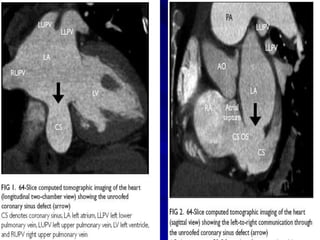

Unroofed coronary sinus anomaly

CORONARY SINUS ASD

Figure 1. Transesophageal echocardiography revealed both atrial and right ventricular

to the dilated coronary sinus (right) at the near longitudinal plane.

Figure 1. Transesophagealechocardiography revealed both atrial and right ventricular enlargement (left), a defect of the partial coronary sinus (middle), and shunt of the left atrium to the dilated coronary sinus (right) at the near longitudinal plane.